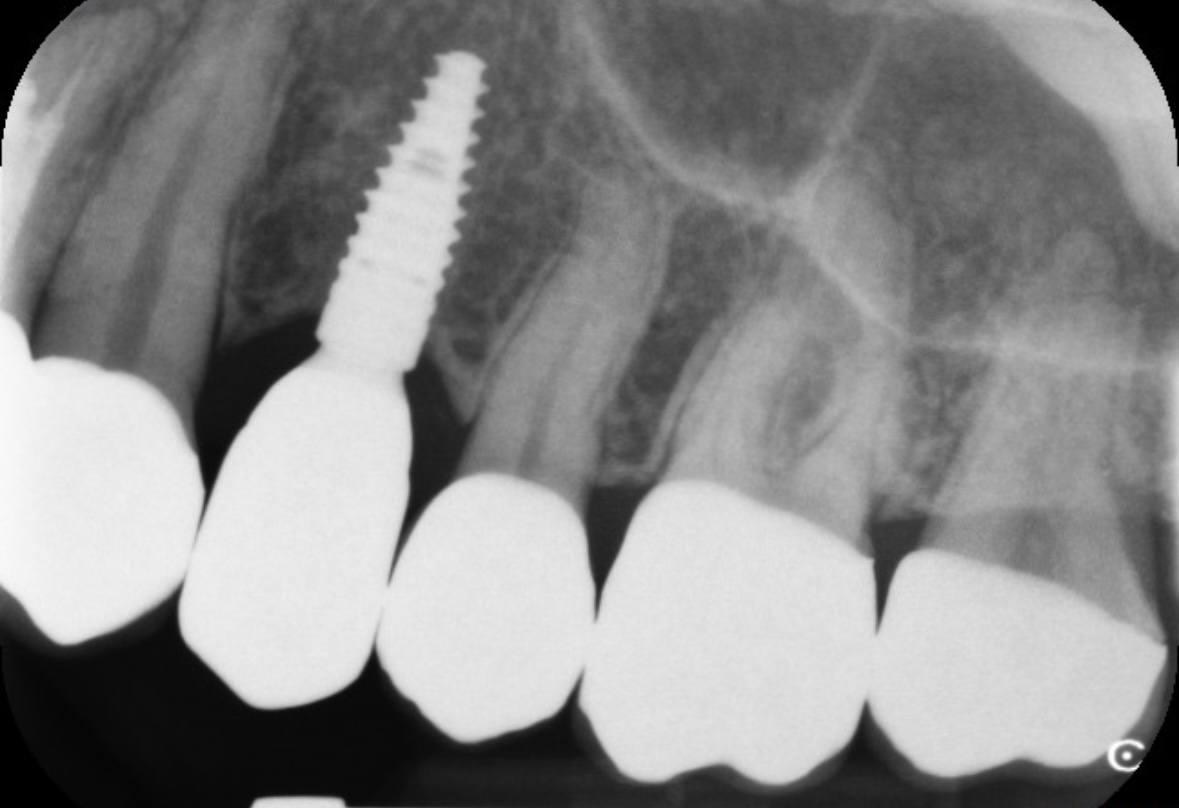

フィステルのようなものができているのは、調べたところ「第一小臼歯」の上でした。

今日また歯医者さんに行き、針のような器具を挿入した状態でレントゲンを撮ってもらいました。

その結果、針がインプラントの手前で曲がっていたため、原因はインプラントの歯ではなく、別の歯にあるとのことでした。

先生のお話では、このできものはフィステルであるとのことで、原因としては側切歯の根の部分に炎症があるのでそこの歯からの可能性が高いそうです。

画像1

画像2